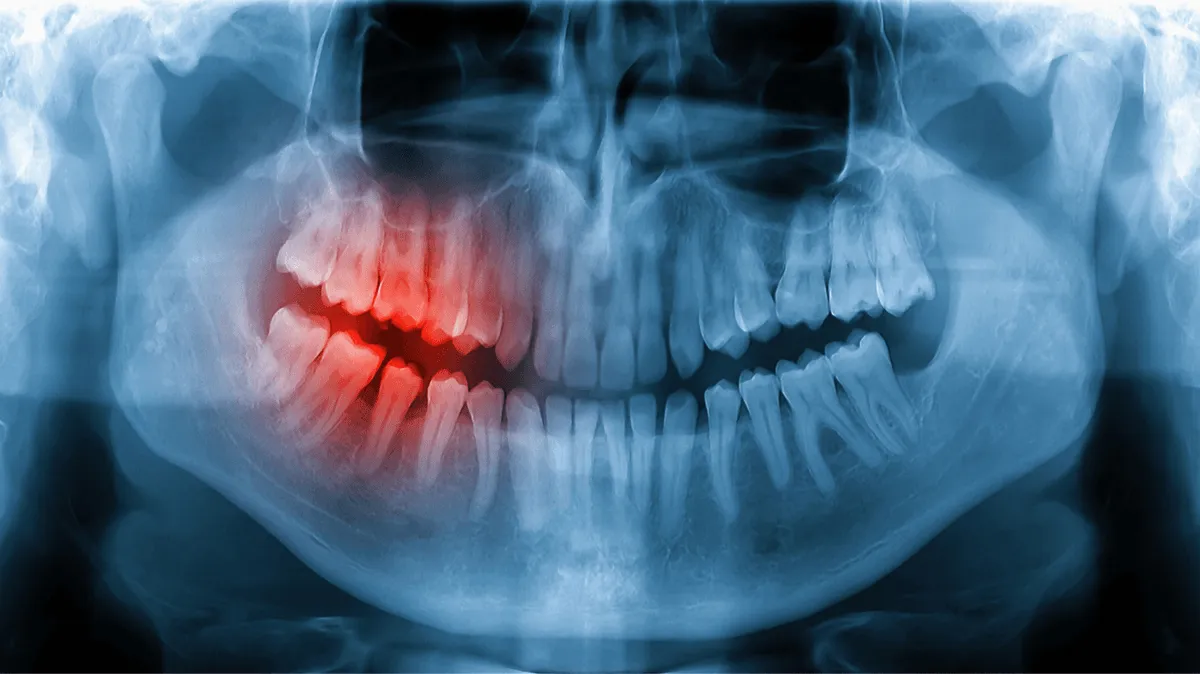

Осматриваем зуб и делаем снимок, чтобы точно определить объём вмешательства и избежать осложнений.